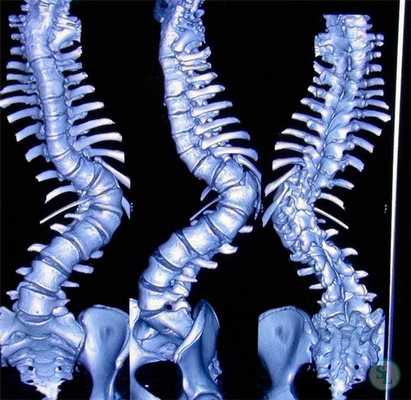

Клинический пример: больная Н., 1999 г.р., прооперированная по поводу сколиотической болезни (рис.1-4):

Рис. 1 Внешний вид больного спереди сзади до операции